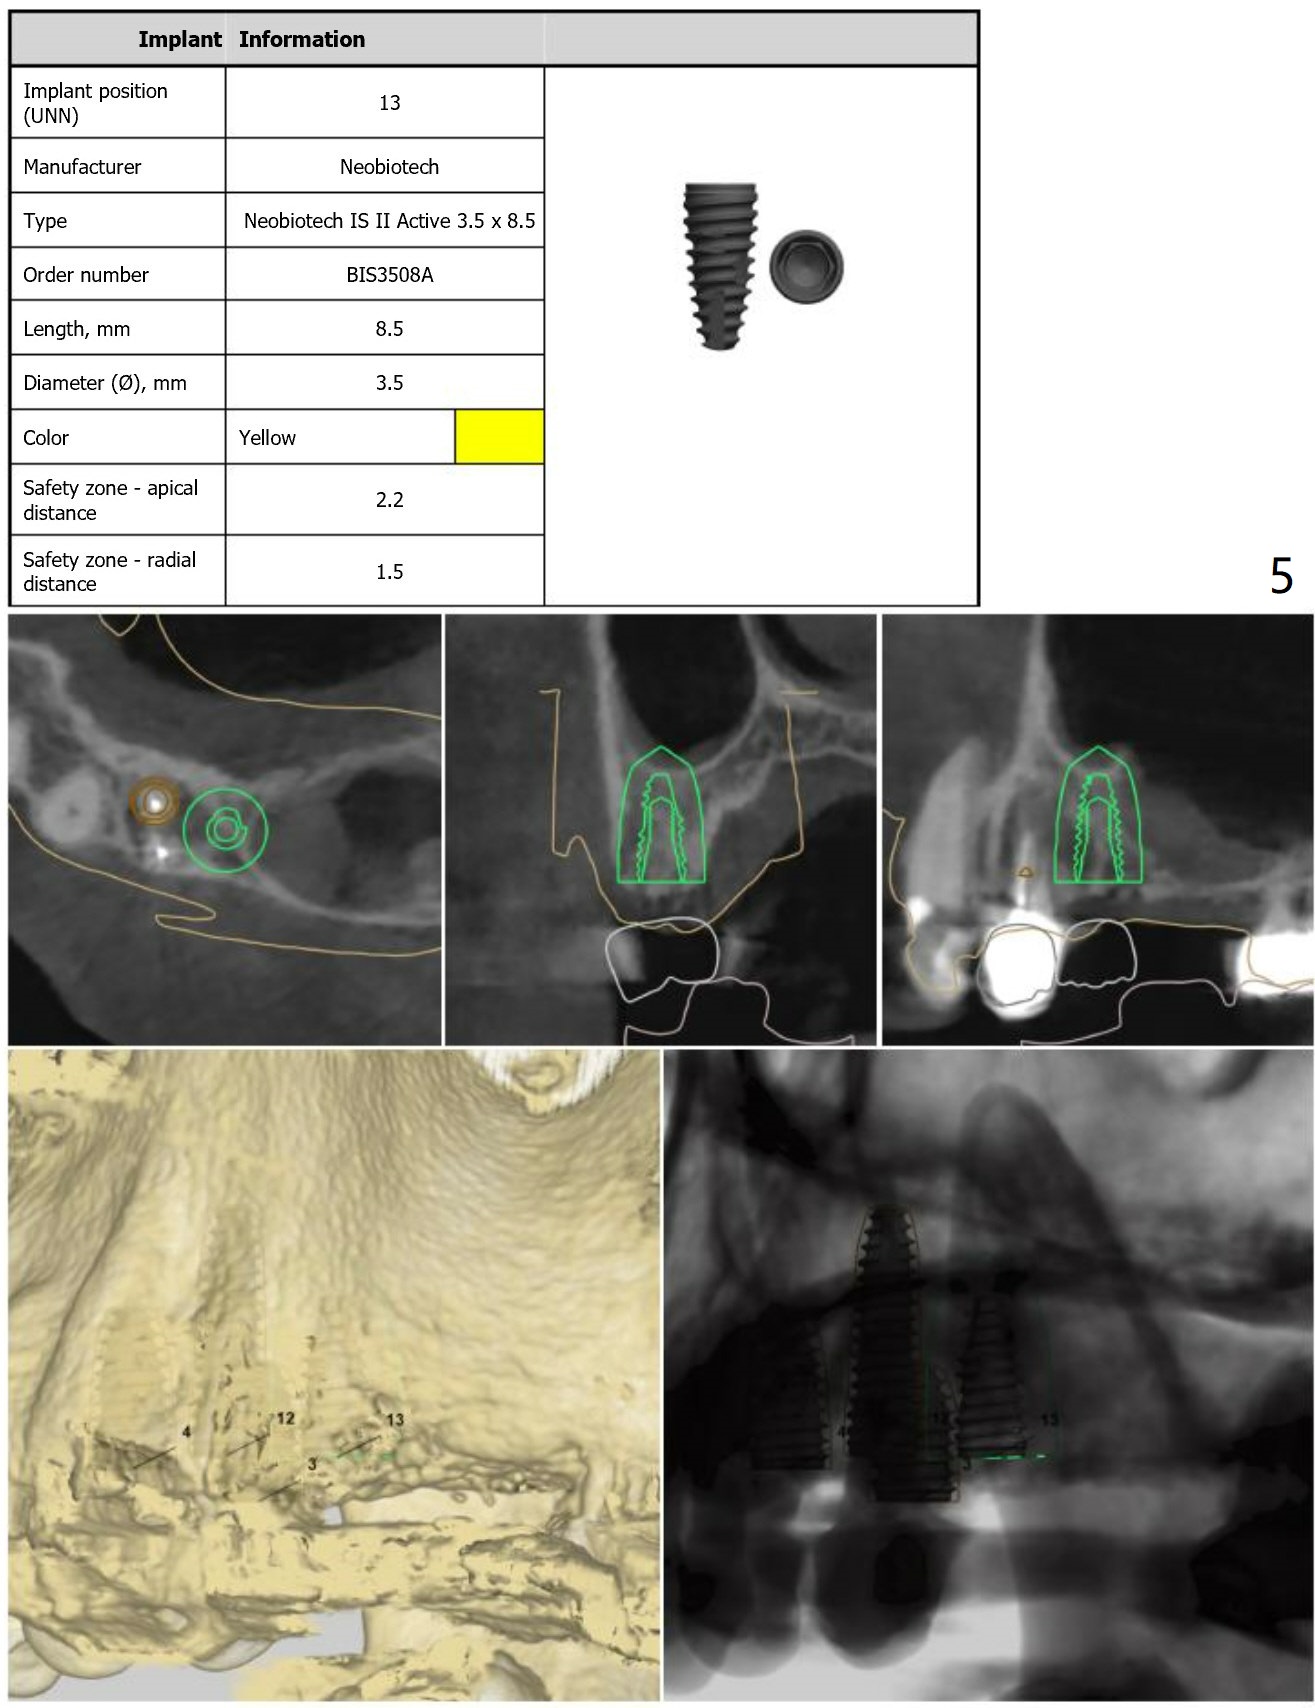

Guide for Sinus Lift

Return to Upper Arch Immediate Implant, Trajectory, No Antibiotic